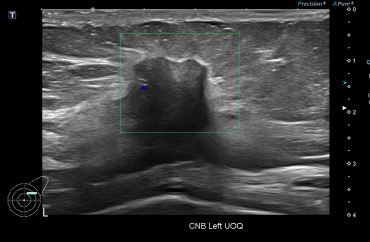

상기환자 외부 건강검진상 유방의 이상소견으로 정밀검사위해 내원하신 70대 여성분으로

좌측유방 혹 총조직검사 시행해 유방암 진단되었습니다